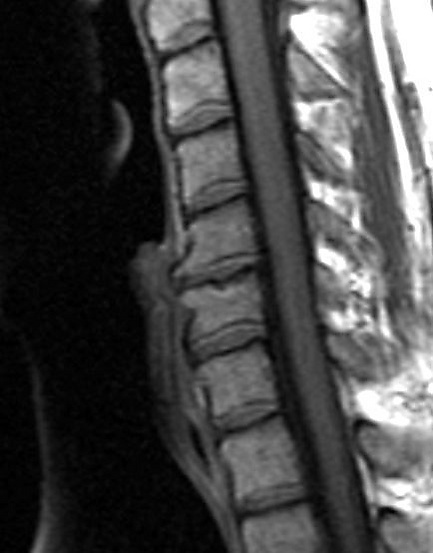

Сжимающие силы, воздействующие на позвоночник в результате механической нагрузки, часто вызывают грыжу диска. В свою очередь, это способствует образованию кистозных образований, называемых узлами Шморля, на верхней и нижней концевых пластинах позвонков[12].

Сара Хенкл (Университет Тулейна) и её коллеги из колледжа Дикинсона и Университета штата Огайо изучили распространённость и интенсивность узлов Шморля у 366 взрослых и 91 подростка из раннебронзового могильника в Баб-едх-Дхра. Цель исследования заключалась в анализе и выявлении различий, связанных с деятельностью, между местной иорданской базой скелетов и другими европейскими базами скелетов. Показатели распространённости сравнивались с такими коллекциями, как пещера Алепотрипа в Греции и местонахождение Змаевец в Хорватии, чтобы проверить наличие региональных различий. Существенных различий в проявлении узлов Шморля между взрослыми и несовершеннолетними из Баб-едх-Дра не было обнаружено. Однако греческие и хорватские образцы скелетов показали значительные различия в частоте встречаемости узлов Шморля по сравнению с иорданскими образцами. Авторы объяснили относительно низкую частоту узлов Шморля у людей из Баб-Эд-Дхра низким уровнем механической активности, связанным с более высоким социальным статусом[13].